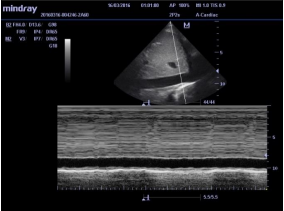

Avaliação do diâmetro veia cava inferior